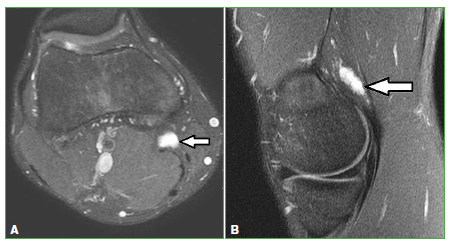

Figura 7.

Lesión del complejo extensor de la mano. Resonancia magnética, secuencias STIR. Cortes sagital (A) y axial (B). Las flechas señalan el cambio de señal adyacente al tendón común de los dedos.

Resonancia magnética de rodilla, secuencia STIR. Cortes axial (A) y sagital (B). Lesión focal en la inserción distal del semimembranoso después del esfuerzo durante la competencia (flechas).

Figura 12.

Resonancia magnética de pie. Secuencia STIR. Cortes axial (A) y coronal (B). Se observa aumento de la señal del quinto metatarsiano compatible con fractura por estrés por sobreuso (flechas).